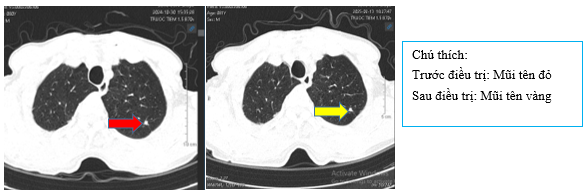

+ Chụp CT ngực sau điều trị

Hình 4:

So sánh phim chụp cắt lớp vi tính lồng ngực trước điều trị kích thước khối u thùy dưới phổi phải từ 40x30mm (mũi tên đỏ) sau điều trị giảm còn 26x20mm (mũi tên vàng)